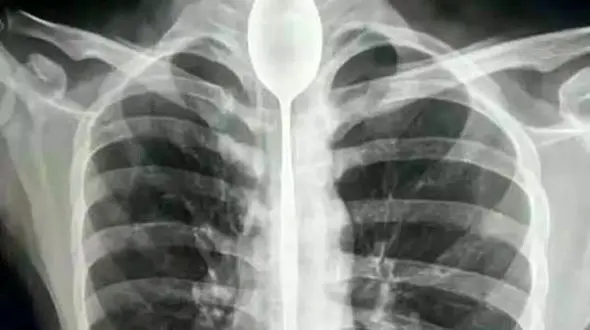

رکنا: مردی در یک شرط بندی احمقانه قاشق 20 سانتی را بلعید و از آنجایی که مشکلی در خوردن و آشامیدن نداشت تا یکسال این قاشق داخل گلوی وی ماند.